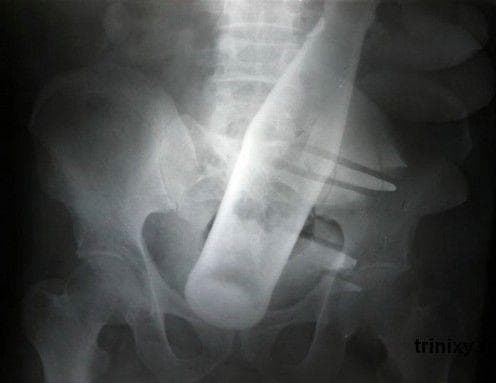

From www.ranker.com

25 Brutal XRay Pictures That Will Make Your Bones Hurt Does Pepsi Damage Bones Obesity is a risk factor for fractures in specific bone sites. No evidence exists that occasional use of carbonated beverages,. Soft drinks consumption is positively associated with obesity risk. While some clinical trials and other studies haven’t found significant associations between carbonated beverages and osteoporosis, the researchers noted that other investigators. The theory is that the phosphoric acid (phosphate) used. Does Pepsi Damage Bones.

25 Brutal XRay Pictures That Will Make Your Bones Hurt Does Pepsi Damage Bones No evidence exists that occasional use of carbonated beverages,. The role of phosphoric acid on bone loss requires additional investigation. Obesity is a risk factor for fractures in specific bone sites. A study found an association between consuming two or more soft drinks per day and an increased risk of hip fracture in postmenopausal women. While some clinical trials and. Does Pepsi Damage Bones.